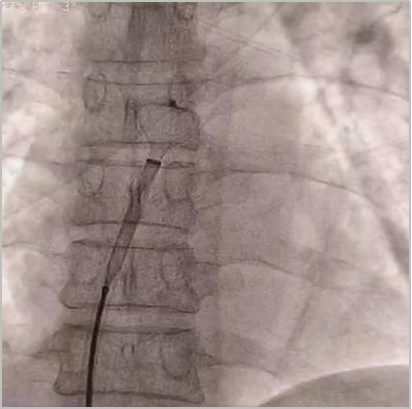

术中所见

释放封堵器

术中测试

释放封堵器后